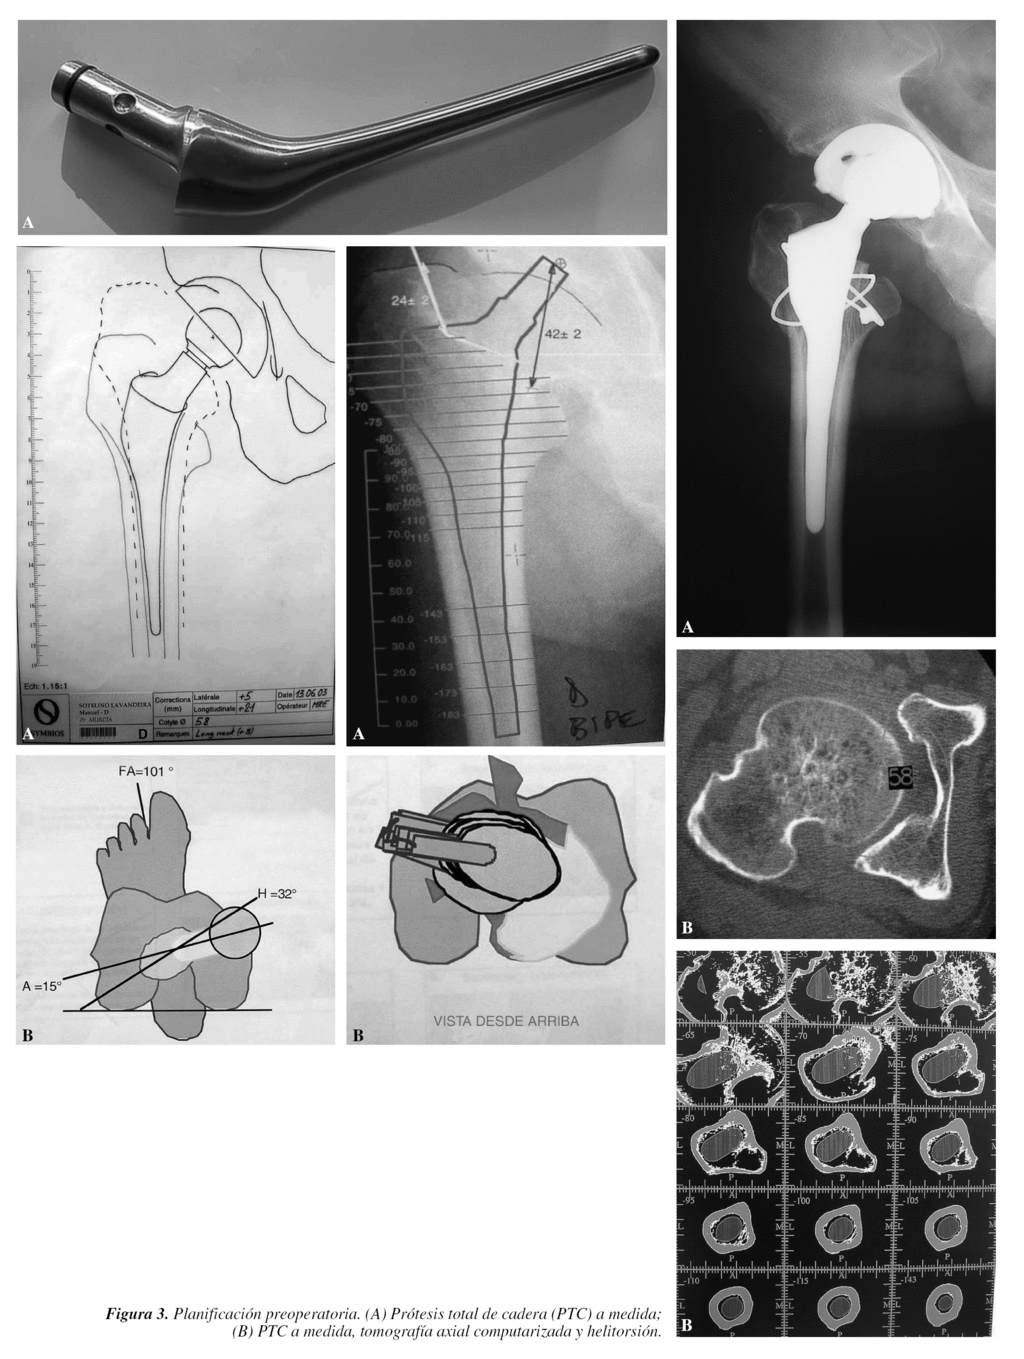

Son las primeras que hay que tener en cuenta y consisten en realizar una correcta planificación con las plantillas (figs. 2 y 3), con el fin de reproducir el acodo lo más exactamente posible, el centro de rotación de la cadera y la longitud del miembro9-12. Los pasos conocidos, pero que conviene recordar, son los siguientes:

Desde el punto de vista práctico, una planificación quirúrgica sería:

1. Nombre, apellidos y número de historia.

2. Edad y sexo.

3. Diagnóstico, tipo de implante cementado (sí/no, mixto).

4. Diferencia, si existe, de longitud de los miembros inferiores (MMII).

5. Cotilo: diámetro en mm, hemisférico, monobloque, perforado, insertos polietileno, cerámica, metal, tamaño interior.

6. Vástago: offset, número, si está cementado o no.

7. Corte del cuello a xx mm por encima del trocánter menor.

8. Longitud del cuello de más de 3,5 mm de diámetro; cabeza en mm metálica/cerámica.

9. Con esta reconstrucción se alarga o no el miembro.

10. Equipo especial que se puede necesitar: a) cotilos y fresas más pequeñas de lo habitual; b) cabezas de 26 mm de diámetro si hubiese que utilizar cotilos pequeños; c) cables de Dall-Miles o material de osteosíntesis en caso de fractura; d) instrumental específico para extraer implante; cortar cerámica, etc.